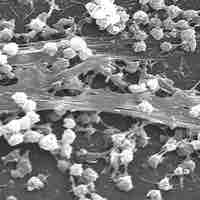

Biofilms and persisters are bacterial communities responsible for chronic diseases and antibiotic tolerance.